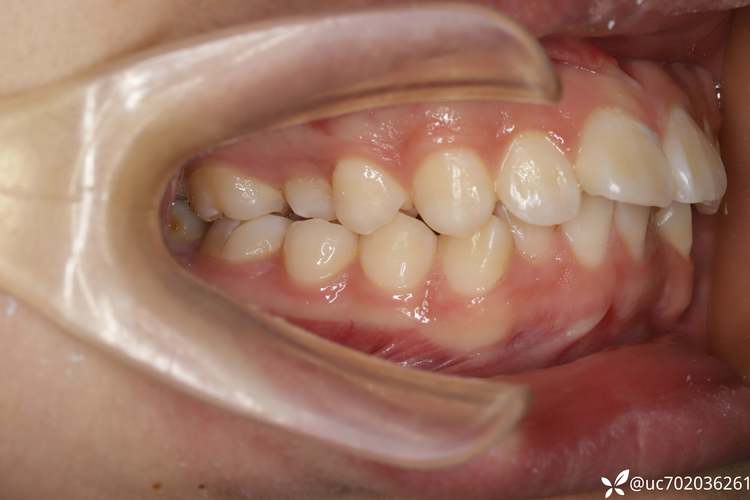

正畸结束后,种牙前需进行系统的口腔检查和评估,以确保种植安全与效果,需通过临床检查评估缺牙区牙龈厚度、邻牙松动度及咬合关系,排除牙周炎、颞下颌关节疾病等禁忌症,影像学检查必不可少,CBCT(锥形束CT)可清晰显示牙槽骨的三维形态、高度、宽度及重要解剖结构(如下牙槽神经、上颌窦位置),帮助医生判断骨量是否充足,是否需要植骨或进行上颌窦提升术,患者全身健康状况也需评估,如是否存在未控制的糖尿病、骨质疏松、长期服用抗凝药物等情况,这些可能影响骨愈合和种植体稳定性,若牙槽骨骨量不足,还需提前进行骨增量治疗,如引导骨再生术(GBR)、自体骨移植等,待骨量达到种植要求后再进行种植手术。